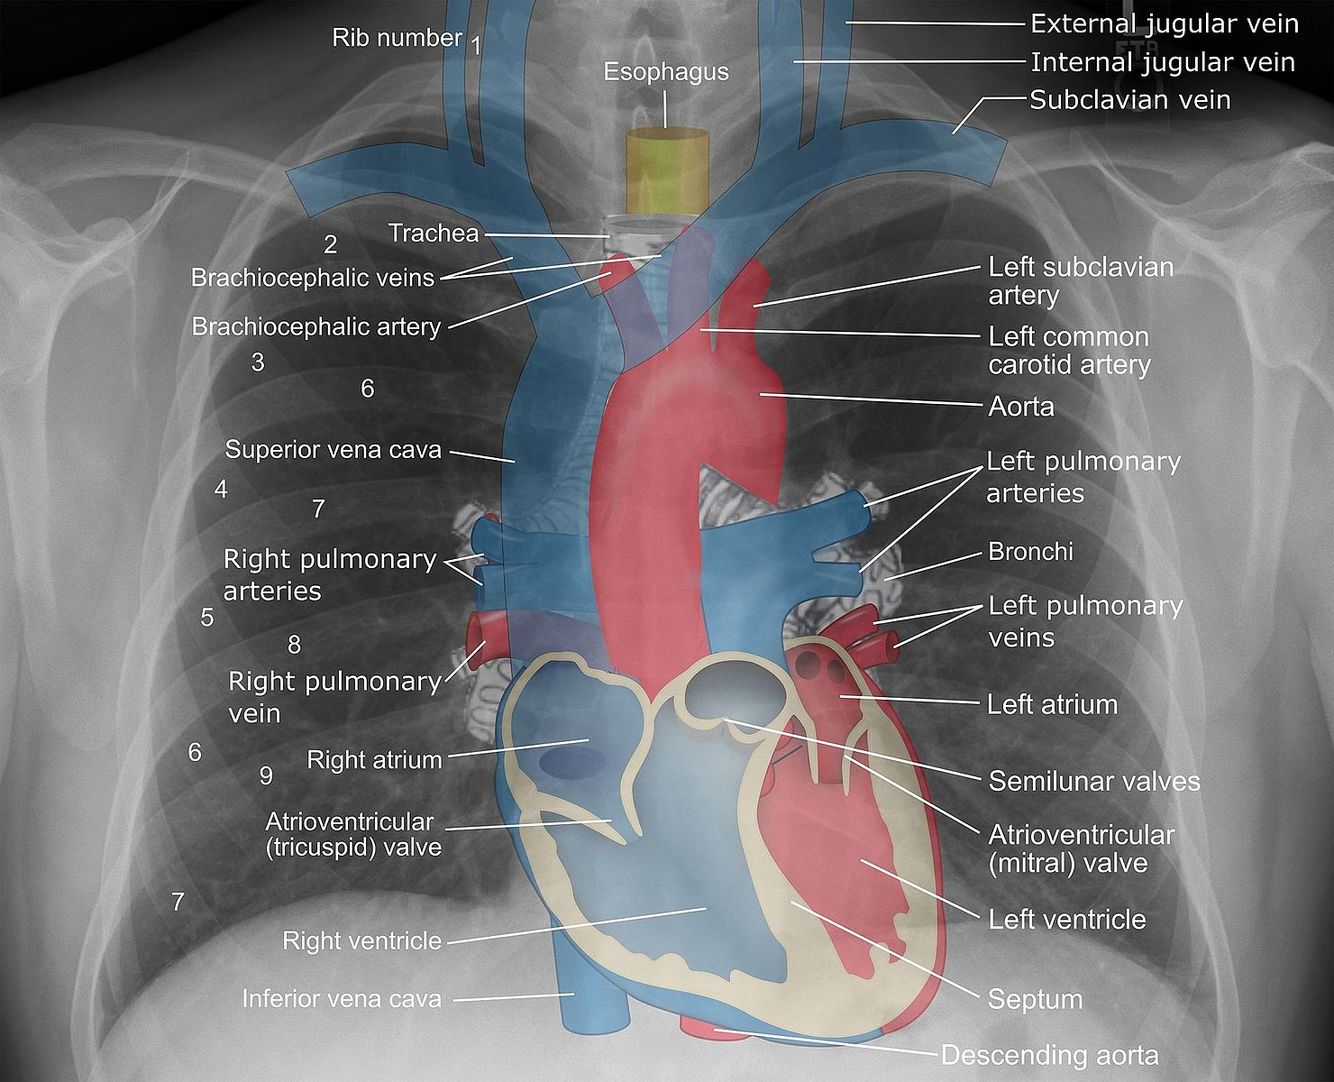

PA View

Beam coming from the posterior and going to the anterior.

Heart size is the most accurate.

AP View

Beam coming from anterior and going posterior.

For patients unable to stand for CXR.

Heart appears bigger b/c closer to the beam.